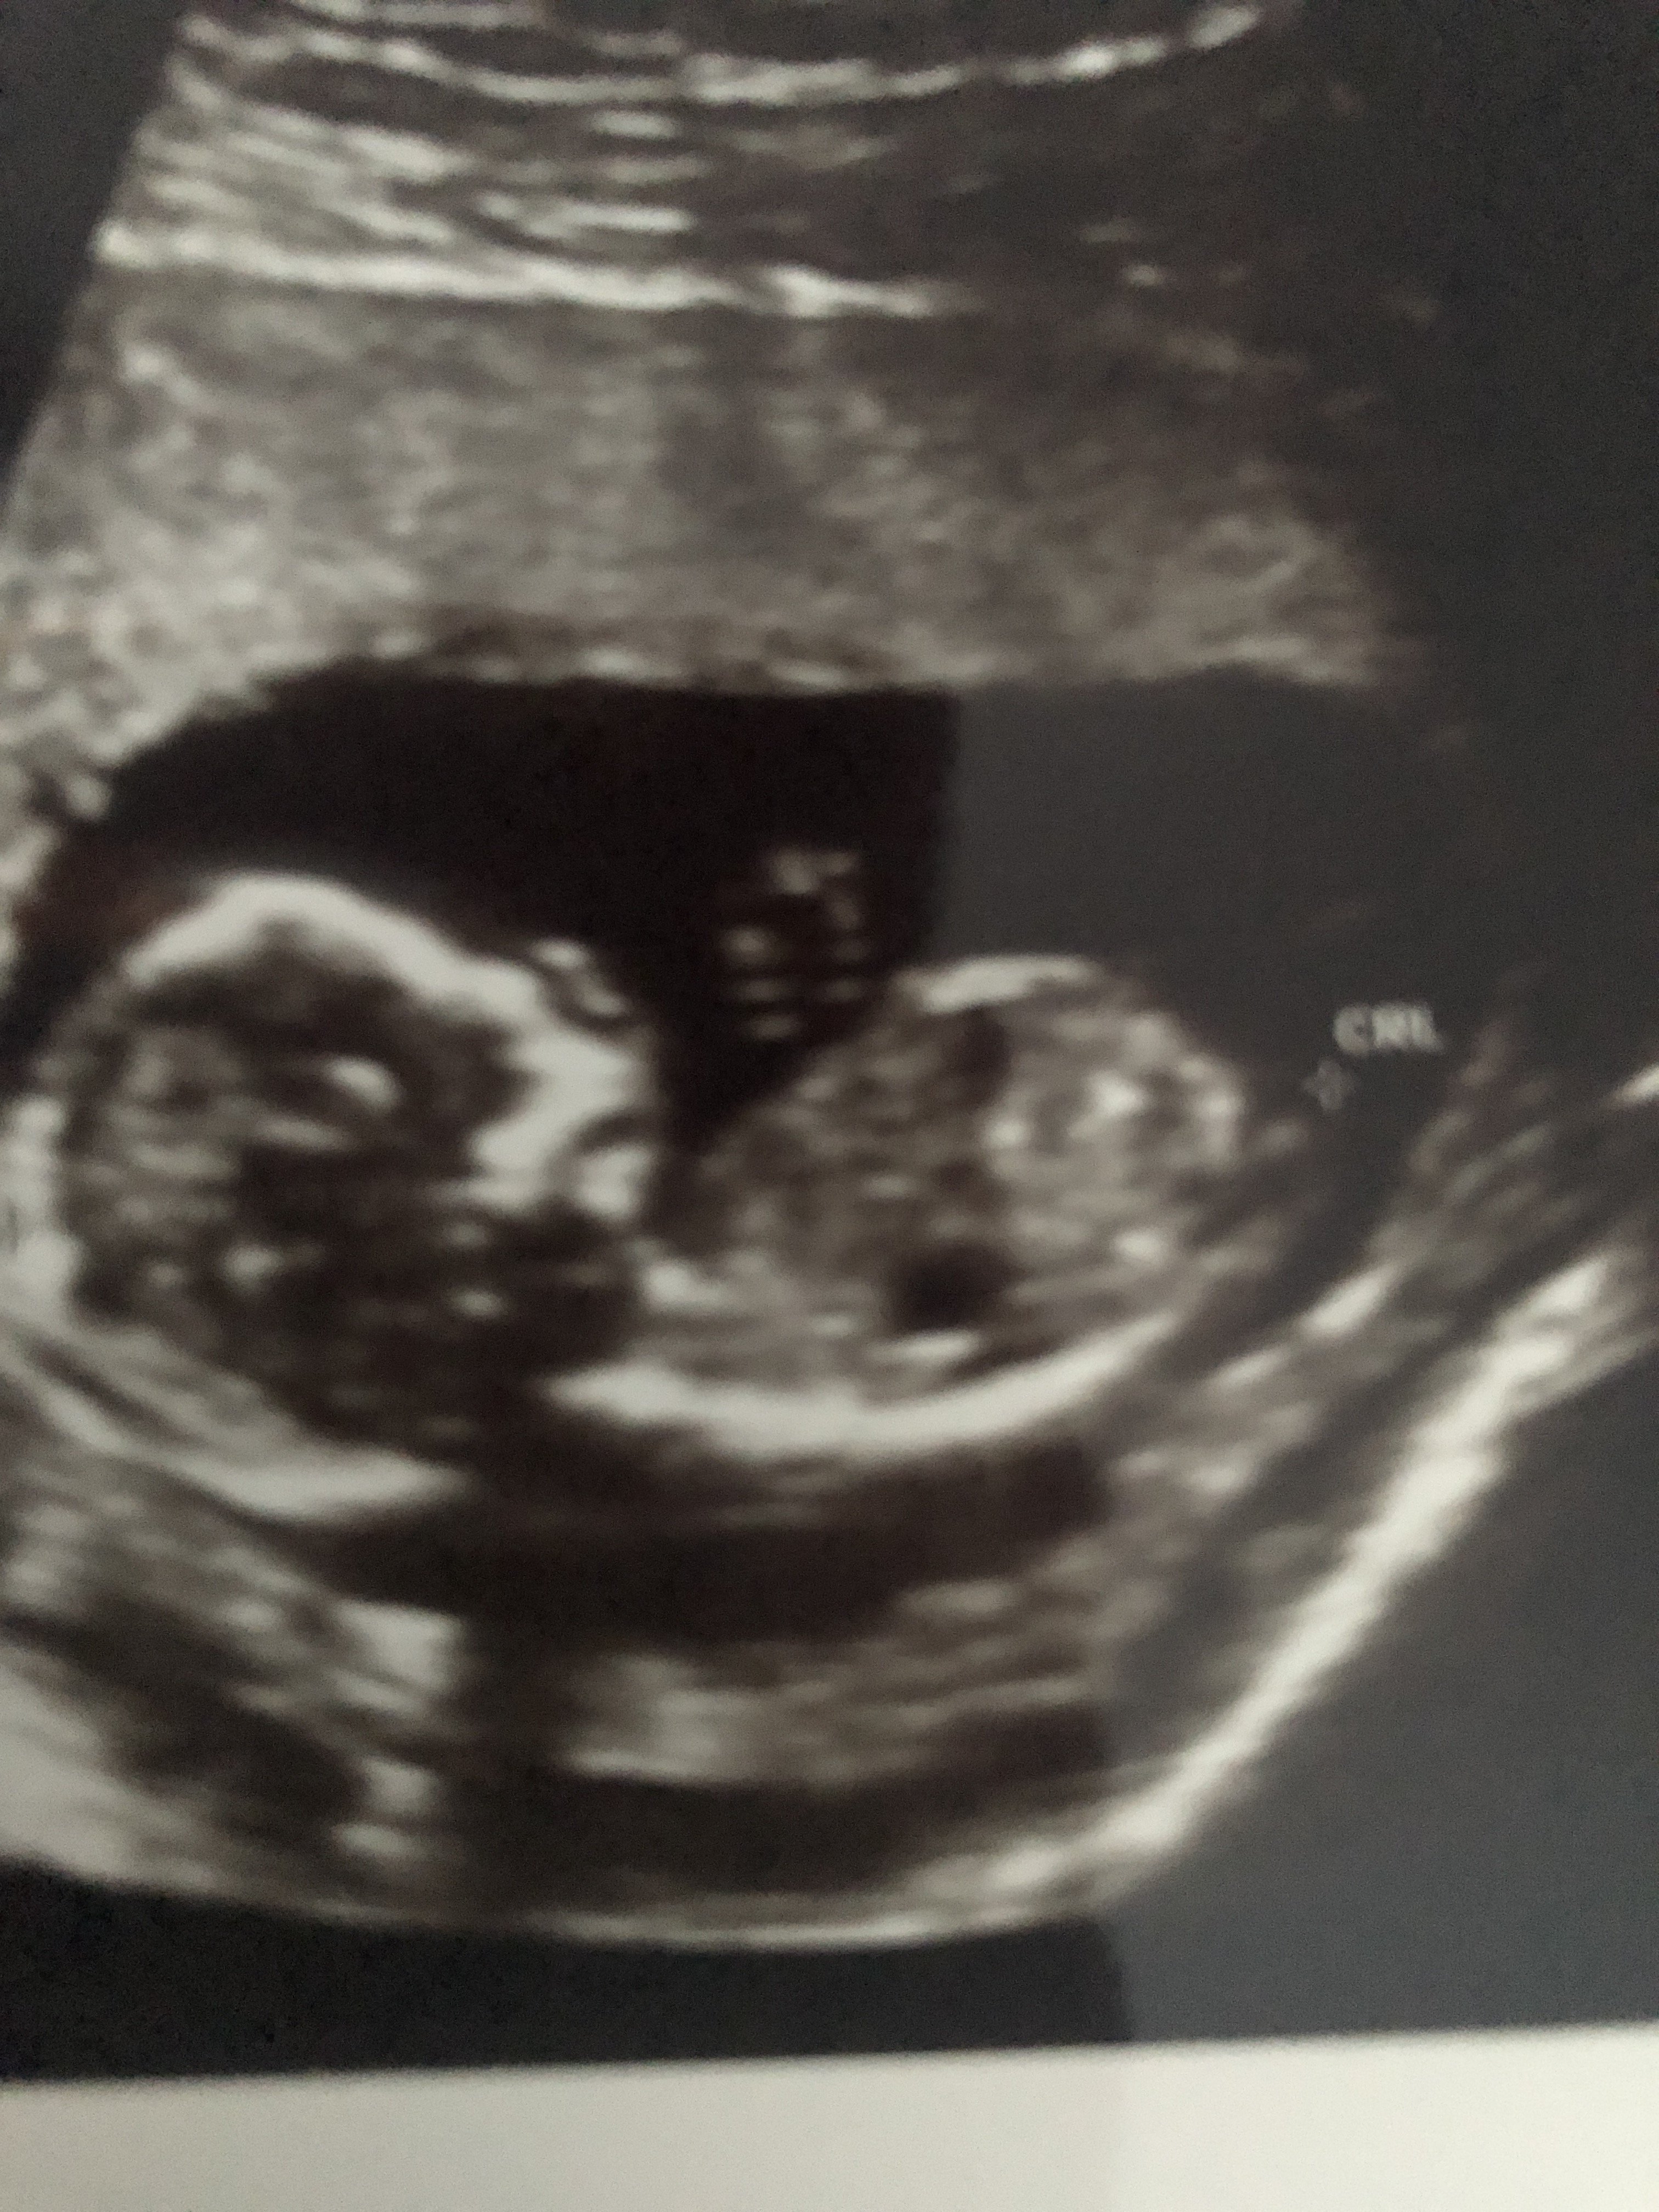

Witam w 19 tygodniu ciąży dowiedziałam się ze będę miała dziewczynkę w 20 tyg okazało się jednak , że to chłopak. Sama już nie wiem bo na jednym usg widać na pewno dziewuche a na drugim chłopca. Może to pempowina ?? Może ktoś mi pomoże rozwiązać ta zagadkę